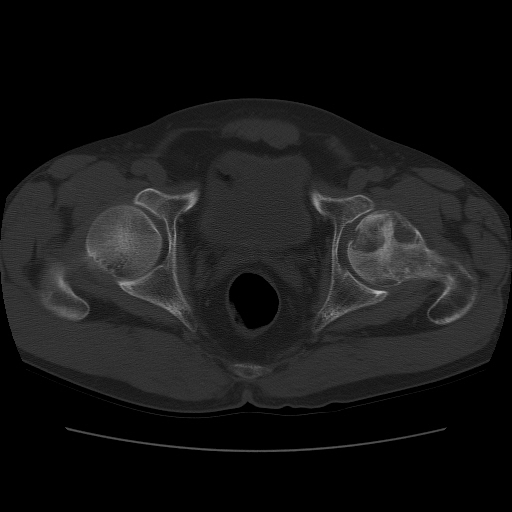

标题: CT11650:左髋病变,请会诊.

左髋疼痛不适近半年,局部无红肿热.无明确外伤病史.黄酒每天二餐.

考虑左侧股骨头缺血性坏死.(常期饮酒引起代谢障碍?)

左侧股骨头缺血性坏死;很典型。

“局部无红肿热.无明确外伤病史.黄酒每天二餐”。考虑左侧股骨头缺血性坏死。